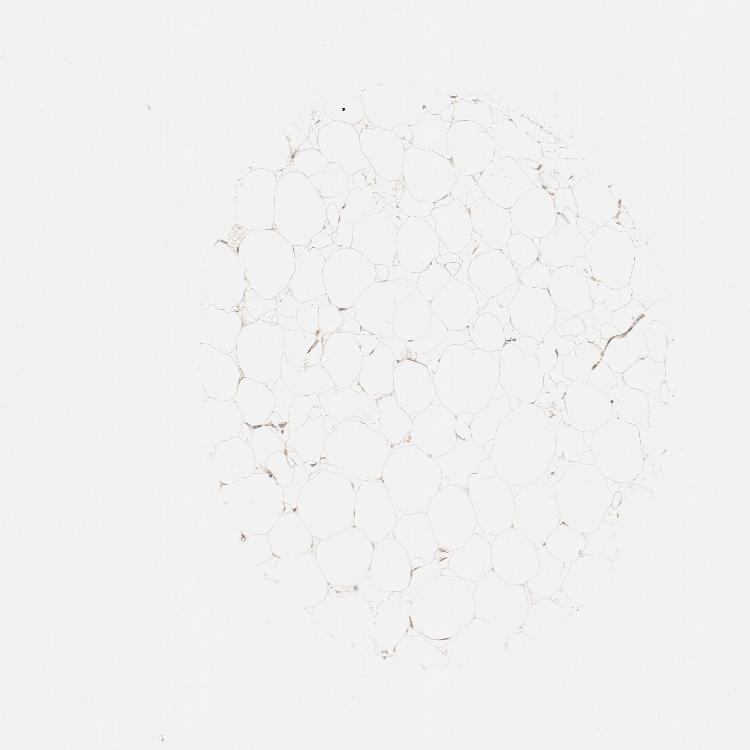

SOFT TISSUE 1 - Antibody stainingi

Antibody staining in the annotated cell types in the current human tissue is reported as not detected, low, medium, or high, based on conventional immunohistochemistry profiling in selected tissues. This score is based on the combination of the staining intensity and fraction of stained cells.

Each image is clickable and will lead to virtual microscopy that enables deeper exploration of all samples and also displays staining intensity scores, fraction scores and subcellular localization as well as patient and tissue information for each sample.

Antibody HPA003742Antibody CAB010443

Fibroblasts Not detectedLow

Peripheral nerve Not detected-